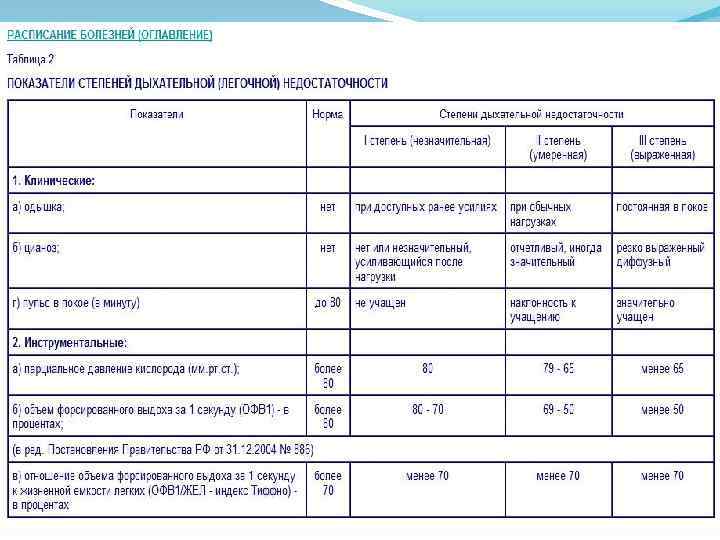

В зависимости от степени тяжести заболевания выделяют его: 1 степень: парциальное напряжение кислорода в артериальной крови (Ра. О 2) 60 -79 мм. рт. ст. , насыщение артериальной крови кислородом (Sa. O 2) 90 -94%; 2 степень: Ра. О 2 40 -59 мм. рт. ст. , Sa. O 2 75 -89%; 3 степень: Ра. О 2 менее 40 мм. рт. ст. , Sa. O 2 менее 75%.

В зависимости от степени тяжести заболевания выделяют его: 1 степень: парциальное напряжение кислорода в артериальной крови (Ра. О 2) 60 -79 мм. рт. ст. , насыщение артериальной крови кислородом (Sa. O 2) 90 -94%; 2 степень: Ра. О 2 40 -59 мм. рт. ст. , Sa. O 2 75 -89%; 3 степень: Ра. О 2 менее 40 мм. рт. ст. , Sa. O 2 менее 75%.

В зависимости от степени выраженности симптомов (для хронической дыхательной недостаточности)различают: ДН I стадии – характеризуется одышкой при умеренных или значительных нагрузках; ДН II стадии – одышка наблюдается при незначительных нагрузках, отмечается задействованность компенсаторных механизмов в покое; ДН III стадии – проявляется одышкой и синюшностью кожных покровов в покое.

В зависимости от степени выраженности симптомов (для хронической дыхательной недостаточности)различают: ДН I стадии – характеризуется одышкой при умеренных или значительных нагрузках; ДН II стадии – одышка наблюдается при незначительных нагрузках, отмечается задействованность компенсаторных механизмов в покое; ДН III стадии – проявляется одышкой и синюшностью кожных покровов в покое.